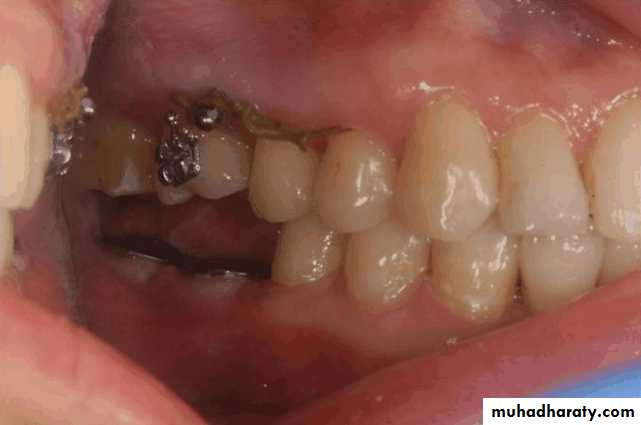

• Treatment over erupted teeth

• If the tooth is extruded above the occlusal plane because of lack of an antagonist –• Treatment

• Moderately extrude tooth – aprox 2mm - enameloplasty.

• If the extrusion is greater than 2 mm or if the tooth does not lend itself to enameloplasty, the placement of a crown is indicated.

• If size of pulp prevent the required tooth reduction endodontic therapy

• If clinical crown length is inadequate crown lengthning

• Orthodontic treatment

• Severely extruded teeth – contacting the opposing ridge & if alveolar bone followed eruption remove the tooth and recontour the bone is necessary

Occlusal plane

Occlusion plane may be irregular because of extrusionOne or more unopposed teeth.

Such conditions require corrective procedures if an acceptable occlusion is to be developed.